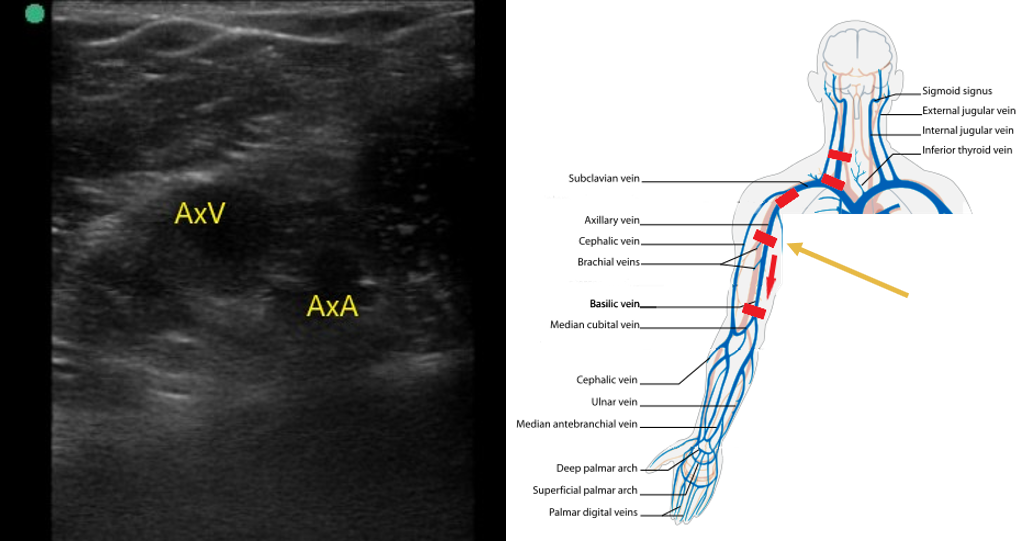

- Next move to the axilla on the same side. With the patient in supine position, have them place their hand on their head to expose the area of interest.

- Identify the subclavian vein as it crosses from the axilla. This area can be difficult to compress. Use color flow in long axis to identify filling defects. Use pulsed wave Doppler to identify normal versus abnormal flow patterns.

- Follow the axillary vein as it traverses into the proximal arm and compress along the way (Fig. 6).

- Figure 6. Axillary artery (AxA) and axillary vein (AxV) in the proximal upper arm.